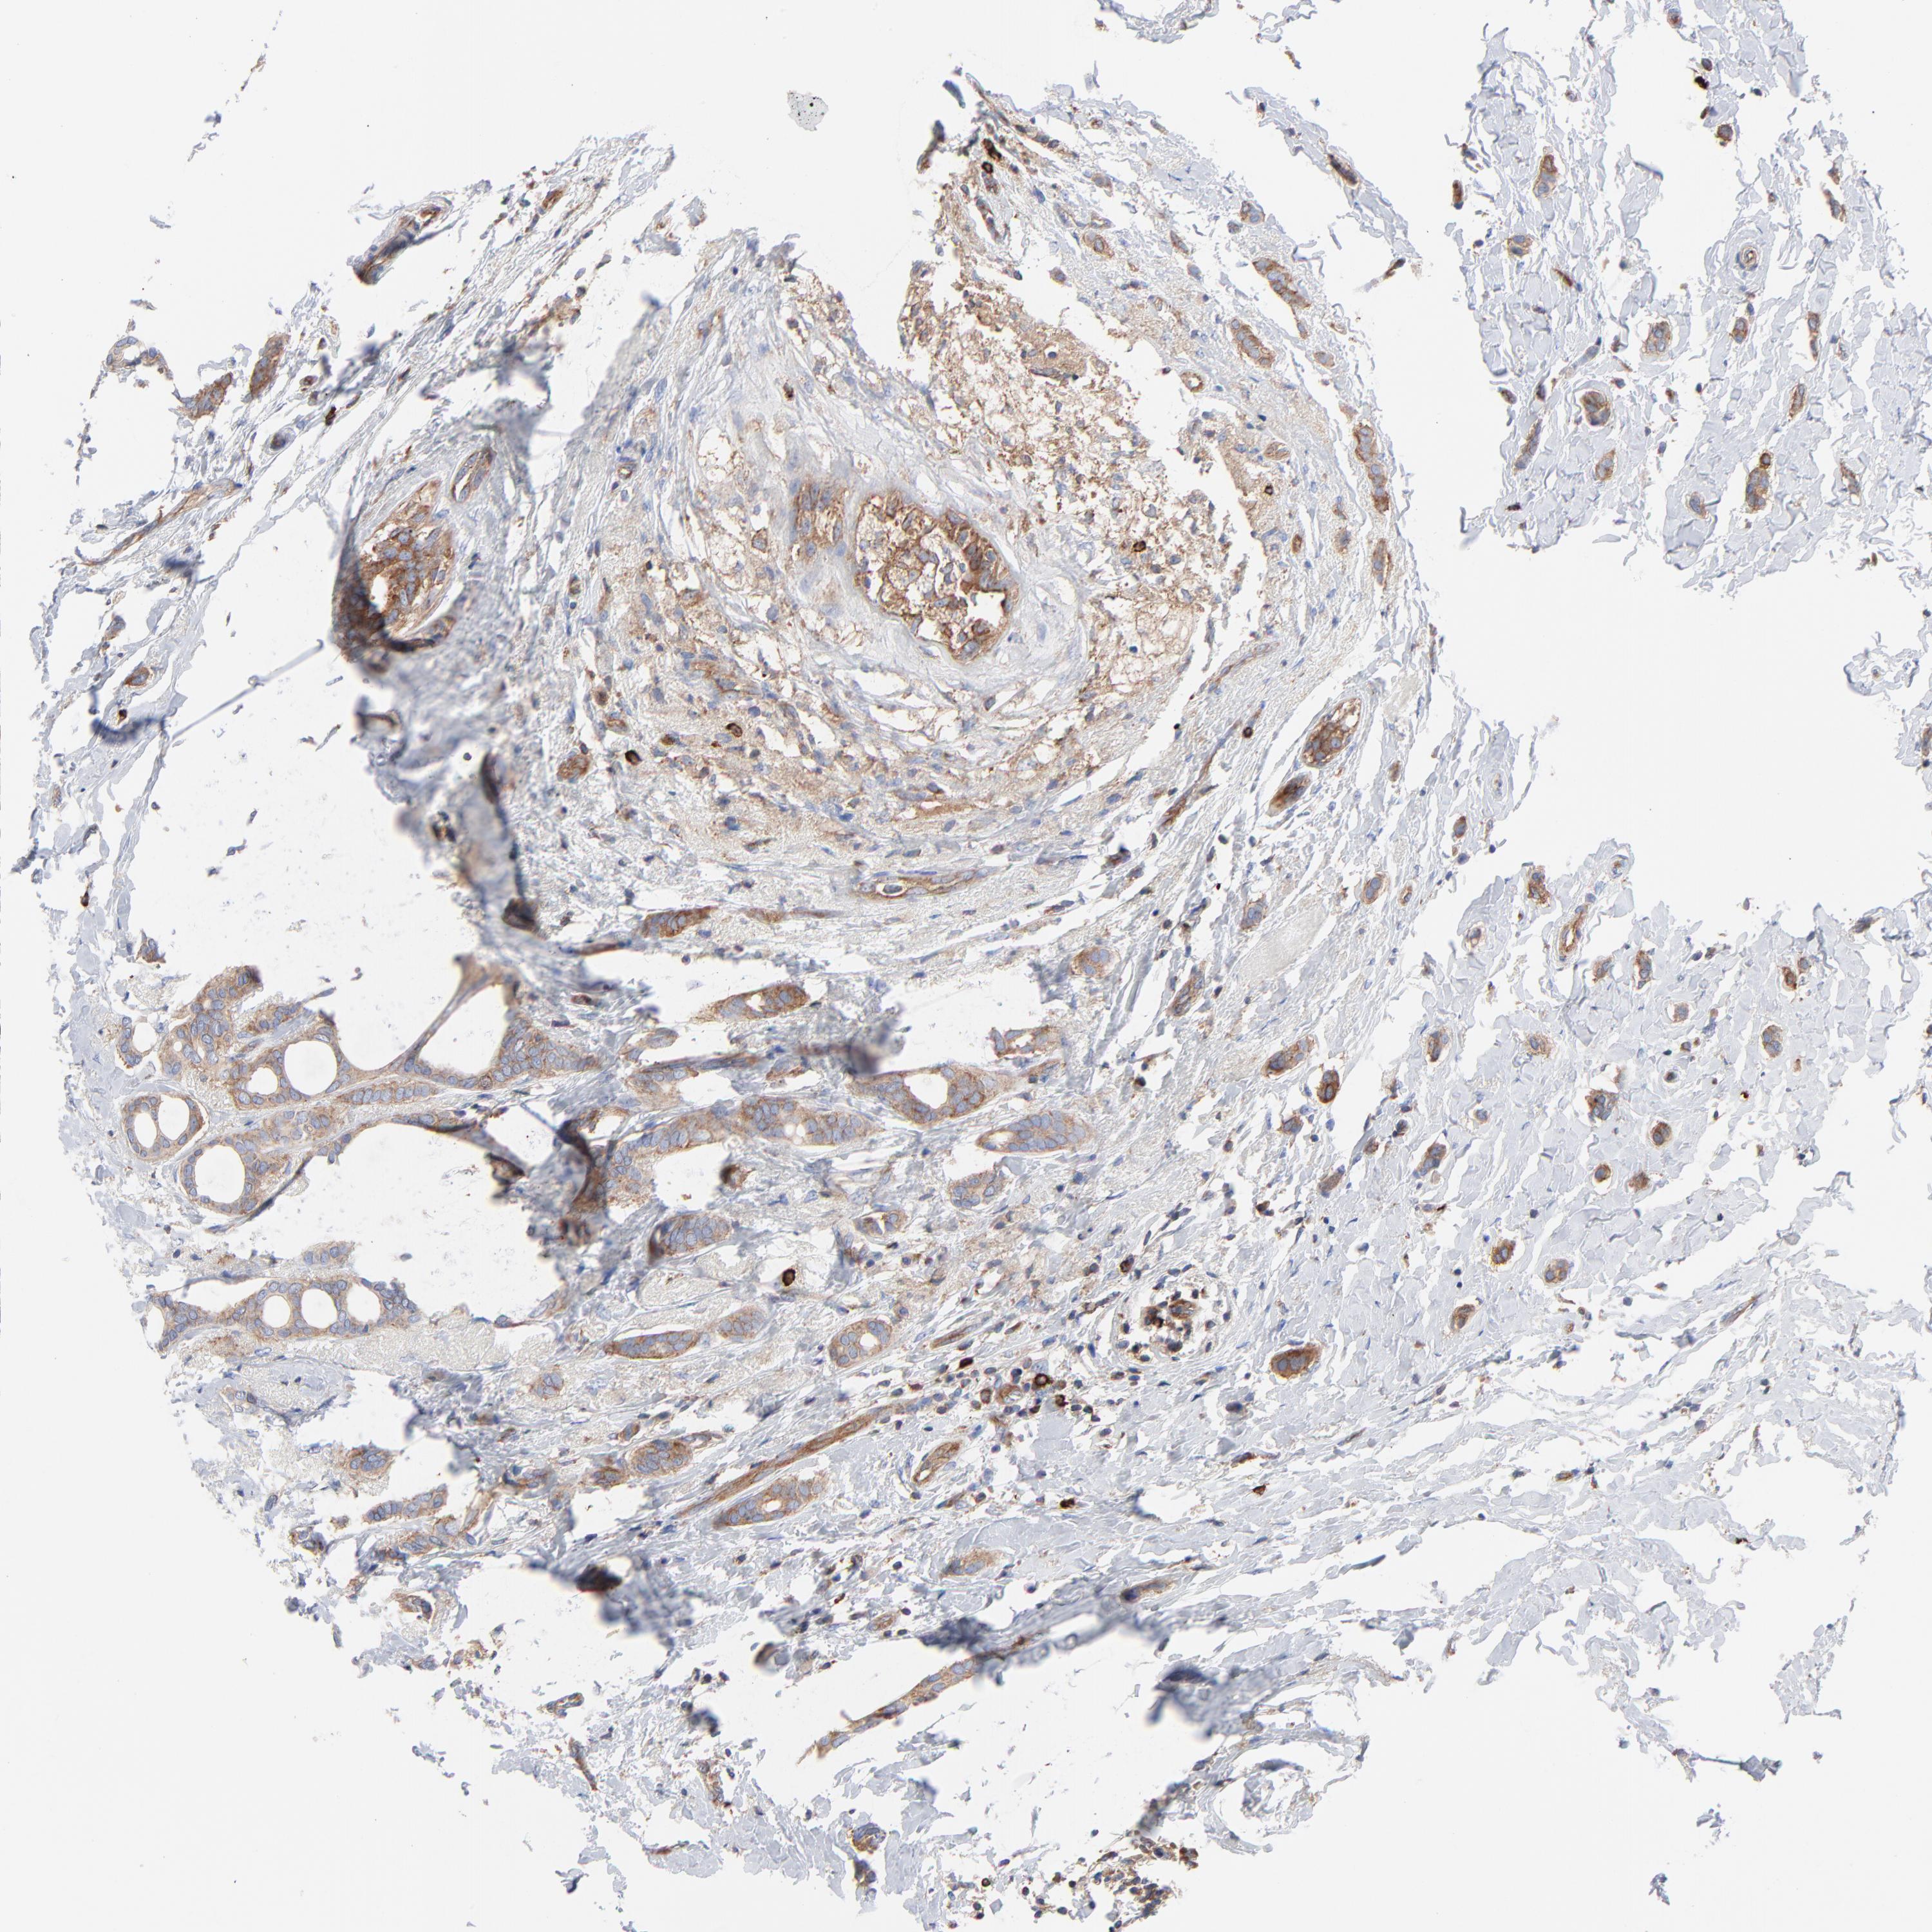

BRCA TCGA BRCA VALIDATION PROTEIN EXPRESSION

ANTIBODIES

AND

VALIDATION